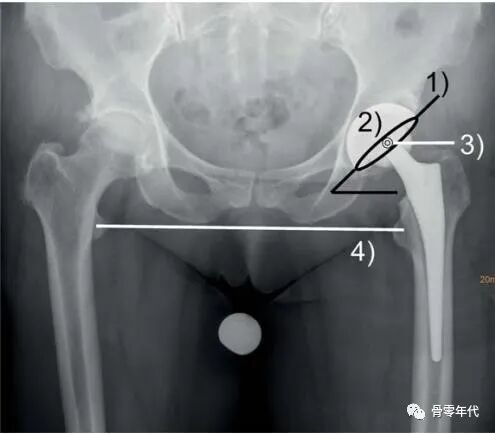

从技术上讲,这些生物力学要求可以通过稳定的假体定位、重建杯外展和前倾、柄前倾、重建髋关节旋转中心、偏移量和腿长来满足(图1),也可以通过使用保留肌肉的外科技术来满足。如果不满足这些生物力学要求,可能会导致机械功能障碍,导致髋关节置换术后不稳定。

图1:全髋关节置换术后的骨盆X光片。为了恢复髋关节运动学,假体定位的特点是牢固的骨支持,重建杯外展(1)和前倾(2),柄前倾和重建髋关节旋转中心,偏移(3)和腿长(4)